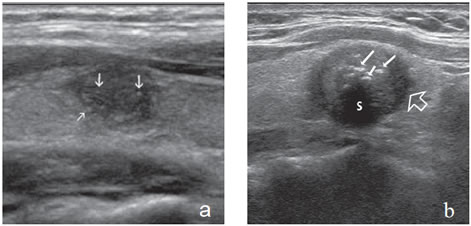

Otro aspecto con muy alta probabilidad de malignidad21 es el de un nódulo sólido relativamente hipoecogénico, con margen mal definido e infiltrativo, con múltiples microcalcificaciones periféricas (Figura 29) y/o microcalcificaciones difusas que aumentan la ecogenicidad de la lesión (Figura 30).

Figura 29. Cáncer papilar de bordes infiltrativos hipoecogénico con

múltiples microcalcificaciones en la zona periférica (flechas).